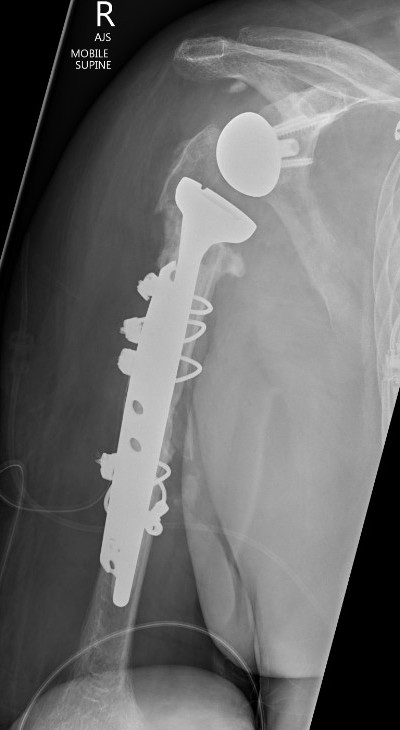

Peri-prosthetic Fracture

Wright and Cofield Classification

Cofield Classfication

A:  Fracture centred at the tip and extends proximally greater than 1/3

B:  Fracture at tip only

C:  Fracture distal to tip of the prosthesis and extends into distal metaphysis

Options Humeral Shaft Fracture

A.  Non operative Management

- well-fixed prosthesis

- acceptable alignment

TSR Periprosthetic FractureTSR Periprosthetic Fracture

B.  ORIF

- displaced tuberosity fractures

- well-fixed prosthesis and fracture distal to prosthesis

Anterolateral approach and plate

C.  Revision

- loose humeral prosthesis / osteolysis

Long stem > 2 cortical diameters past fracture

aTSA fracture 1aTSA fracture 2revTSA following fracturerevTSA for fracture